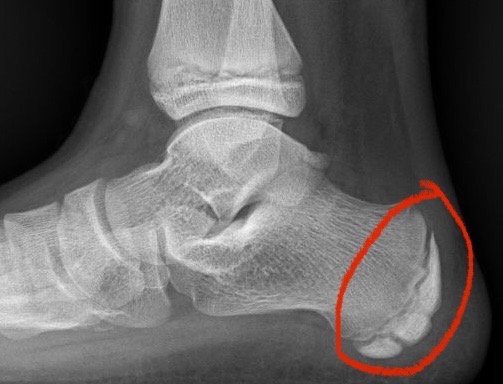

Infiltraciones en el dolor de talón: ¿cuándo, cómo y por qué?

El dolor de talón es el motivo de consulta más frecuente y que más desespera a los pacientes. Con respecto a las infiltraciones surgen muchas dudas y es que es necesario saber qué , cuándo y por qué ? ¿Las infiltraciones son buenas o malas? Las infiltraciones no son...